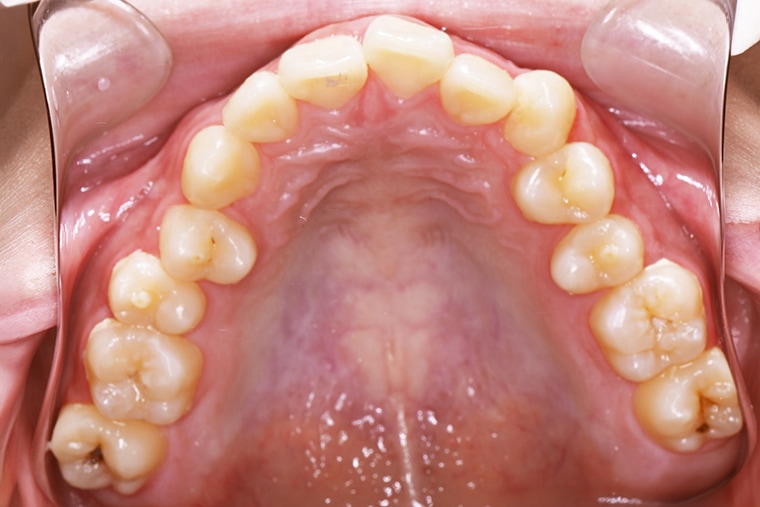

BEFORE